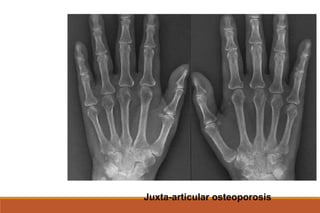

RHEUMATOID ARTHRITIS

X-rays

◦ The earliest changes occur in the wrist or feet and consist of soft

tissue swelling and juxta-articular demineralization.

◦ Later, diagnostic changes consisting of joint space narrowing and

erosions develop. The erosions are first seen at the ulnar styloid

and at the juxta-articular margin, where the bony surface is not

protected by cartilage.

Juxta-articular osteoporosis